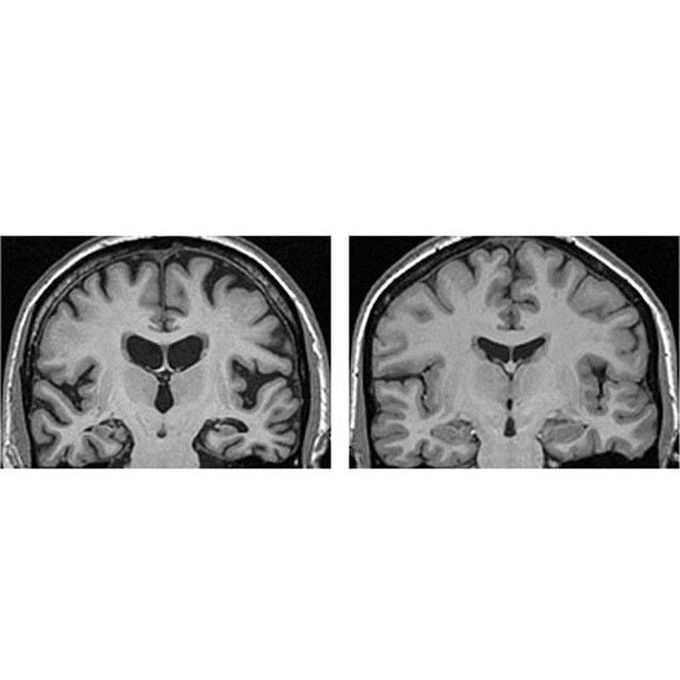

Comparison of a normal human brain MRI (right) and an MRI (left) taken from a patient with a well-known disease - Alzheimer's disease! Loss of brain tissue (atrophy/degeneration) is seen well, shrinkage of the cerebral gyri of the temporal and parietal lobes, as well as the corpus callosum, fornix, caudate nucleus, and the hippocampus. All of which causes the dilation of the lateral and third ventricles (in the middle). Alzheimer's is a chronic neurodegenerative disease, and it's the most common cause of dementia, a general term for memory loss and other intellectual abilities. It's important to know that it's a progressive disease, where dementia symptoms gradually worsen over a number of years. In its early stages, memory loss is mild, but with late-stage Alzheimer's, individuals lose the ability to carry on a conversation and respond to their environment. The cause is poorly understood. It is believed that a build-up of beta-amyloid plaques and neurofibrillary tangles in the brain are associated with the disease. Other risk factors include a history of head injuries, depression or hypertension. No cure for Alzheimer's, but there are medications that slow the progression of the disease and manage the symptoms.